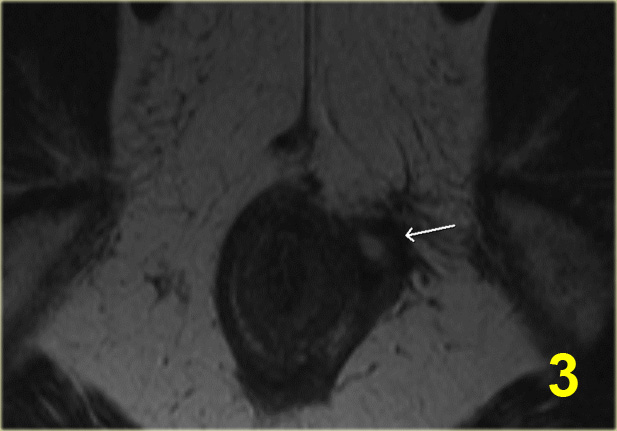

Bên trái là hình ảnh cắt ngang chuỗi xung T2W và T2W kết hợp xóa mỡ của một đường rò xuyên cơ thắt.

Khuyết hổng qua cơ thắt trong và cơ thắt ngoài ở vị trí 6 giờ hiện rõ và nổi bật hơn trên hình ảnh xóa mỡ.